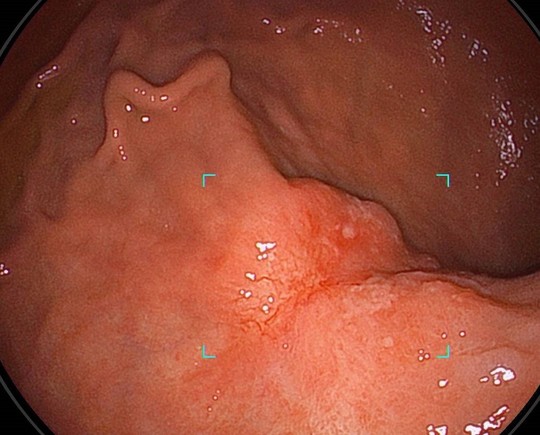

AI(人工知能)内視鏡検査支援システムによる最新の内視鏡検査

山クリニックでは経験豊富な内視鏡専門医とAI検査支援システム併用の検査を胃カメラでも大腸カメラでも両方の検査で受けることができます

①病変をAIの目で瞬時に捕捉

経験豊富な内視鏡専門医の目に加えて、疲れ知らずのAIが胃病変を瞬時に捕捉し追いかけます。

大腸カメラ(下部消化管内視鏡検査)

AIと専門医の目で瞬時にポリープを発見

NBI画像をAIと専門医の目で診断

AI内視鏡検査支援プログラム導入のお知らせ

AI内視鏡検査支援プログラムCADEYE(FUJIFILM)を2025年4月より導入しました。国立がん研究センター内視鏡部での経験豊富な5名の専門医で検査を行っておりますが、さらにAI検査支援も加えてより質の高い内視鏡検査を行います。AI内視鏡をご希望の方はお気軽にお問い合わせください。

AI内視鏡診断システム導入のお知らせ

AI内視鏡診断支援システムEndoBRAIN(ワンモニター型)を2024年11月より導入しました。北関東エリア(群馬/埼玉/栃木/茨城/千葉)では初導入(オリンパス社調べ)となります。国立がん研究センター内視鏡部での経験豊富な専門医で検査を行っておりますが、さらにAI診断も加えてより質の高い内視鏡検査を行います。AI内視鏡をご希望の方はお気軽にお問い合わせください。詳しくはこちら